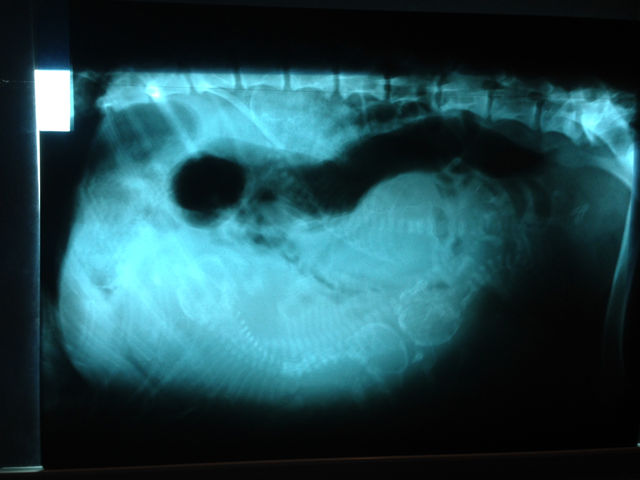

Birth